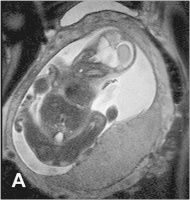

Plazenta - 26. SSW

Abbildung 6a-b: A. Normale, homogene und glatt begrenzte Plazenta in der 26. SSW. B. Gleiche SSW, die Plazenta hat jedoch eine pathologisch unruhige Binnenstruktur und eine unregelmäßige Oberfläche. Der Fetus weist eine Wachstumsrestriktion auf.